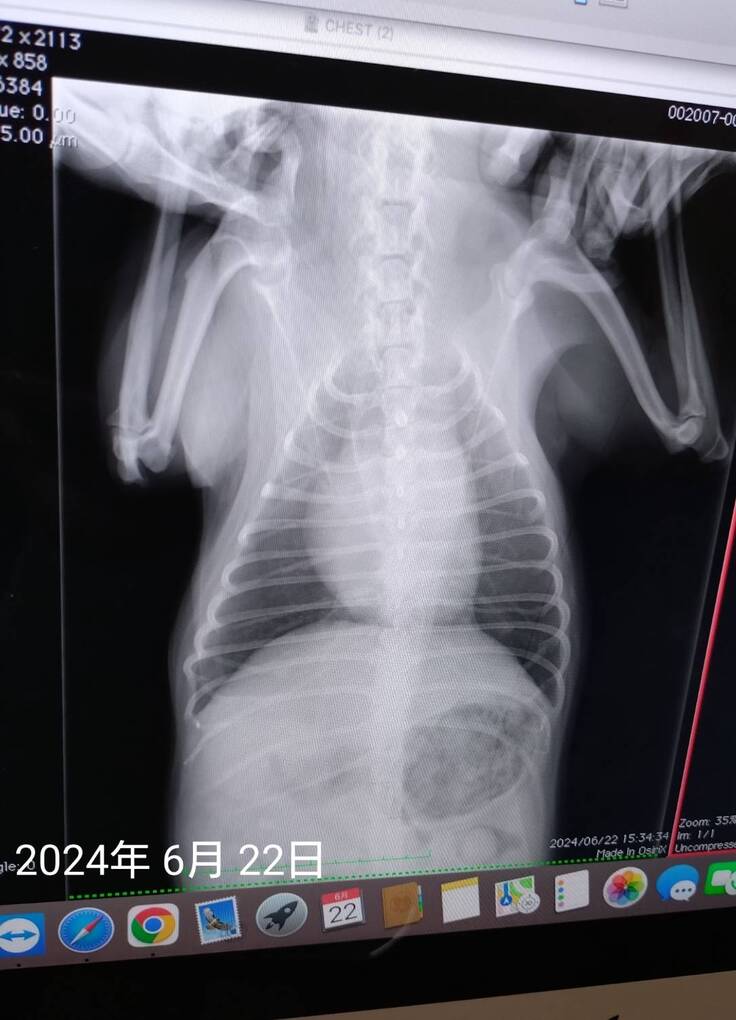

6月22日にかかりつけ病院を受診し、肺の音、心臓の音は前に肺水腫、肺炎、気管支炎、扁桃炎になったときと比べ、肺などは問題ない状態でした。

レントゲンも5月に検査した結果と見比べても問題なく、血液検査の結果、CRPの数値が少しだけ高い状態でした。(肺水腫、肺炎ひどかったときは白血球の値も異常、CRPの数値も7で振り切れてたが、今回1.1)どこかに炎症が起きてる可能性は否めない数値でした。